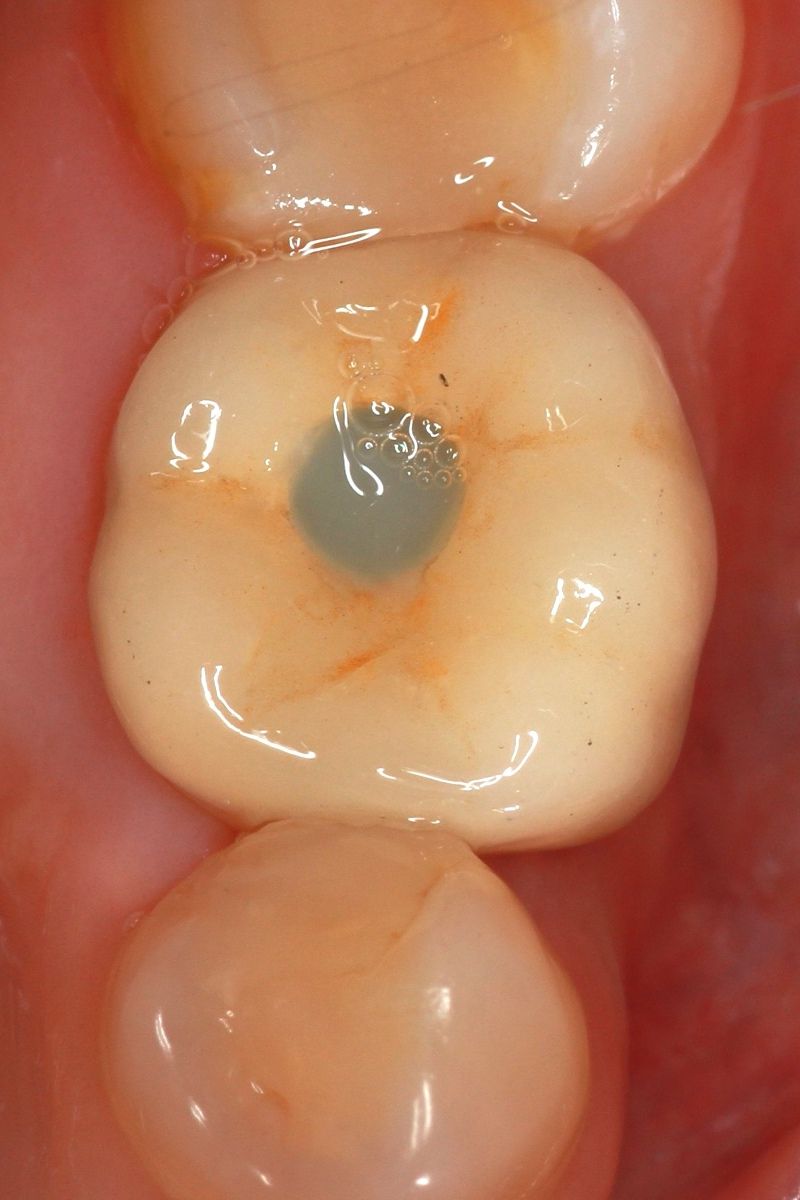

Installing the crown

We install an individual abutment, fix the crown

In our clinic, implantation is often accompanied by an additional increase in bone volume and an increase in the height of soft tissues. This is done to preserve aesthetics and preserve the implant. So that the implantation site is not visible, we create a single level of the gum, the same as that of the adjacent teeth. And the same is done to prolong the life of the implant, because it is the gum, which is tightly attached to the crown, that is the barrier that protects the implant from bacteria.